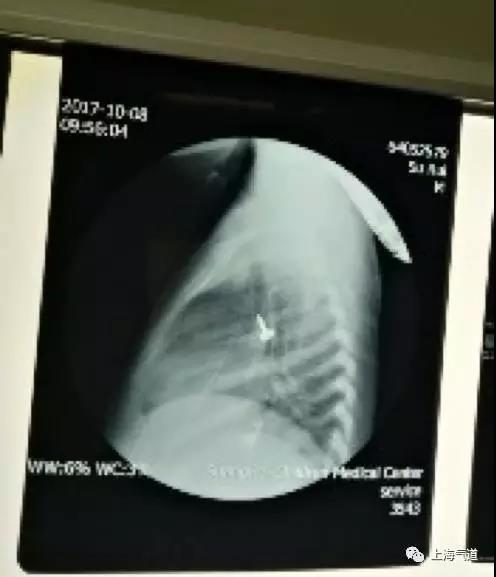

做了三个食道异物后,耳鼻喉科值班医生告诉我们还有一个老年患者声门口异物。患者76岁, 系下颌骨肿瘤切除和气管切开术后,有放疗史,张口受限,当地胃镜检查示声门口异物并嵌顿无法取出(图1A),术前我院CT检查显示异物义齿嵌顿于声门口。李医生带我一起读片,发现声门口没有插管空间,如果麻醉诱导后插管很可能将异物推入气管内造成气管异物,麻醉风险很高。再和外科医生沟通决定麻醉方案,我们首先预给充足氧气后麻醉诱导(图1B),诱导后不进行气管插管,外科医生直接去取异物,如果异物取出失败或者需要较长时间,准备进行紧急环甲膜穿刺并利用手控喷射装置给氧气(图1C),如果氧合不能维持外科医生则行气管切开术。按照既定方案诱导后外科医生直接去取异物,异物嵌顿明显,旋转180度后仍然难以取出异物。外科医生担心撕裂声带造成患者发音和术后气道梗阻,调整角度后继续并最终取出异物(图1D)。观察到渗血明显,面罩通气后,外科医生予以肾上腺素棉片压迫止血。术毕置入喉罩并进行辅助通气,一刻钟后患者苏醒,完全清醒状态下拔除喉罩。患者声嘶明显,复苏无明显呼吸困难后送返病房,嘱床旁心电监护并观察是否有呼吸困难。外科医生感叹麻醉有惊无险,事实上我们的从容处理得益于主任一直推动科室进行的声门上气道和紧急外科气道等培训项目的持续进行。